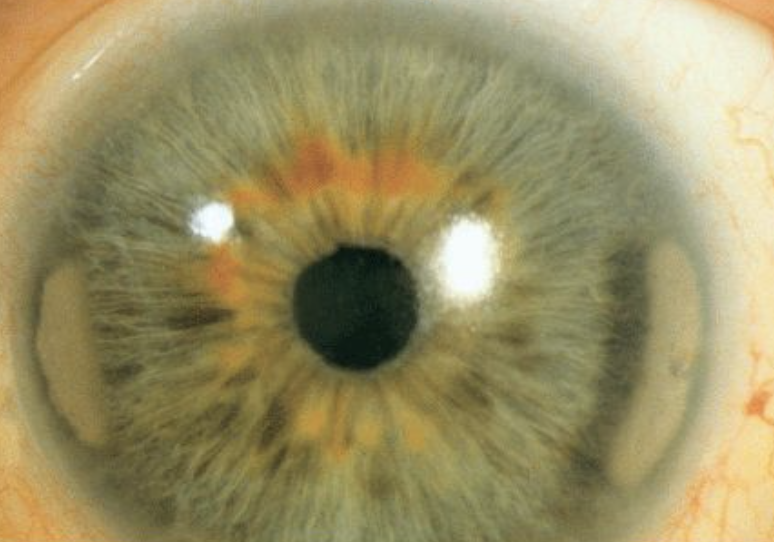

Kaiser Fleischer ring - copper accumulation in Wilsons disease

A, B, and E: Posterior embryotoxon (yellow arrows), increased intraocular pressure in the right eye. C: Iris transillumination and atrophy (red arrow). D and E: High iris strands adherent to the posterior embryotoxon, ranging from fine threadlike strands to broad bands of iris tissue (green arrows)

Axenfeld Rieger Syndrome

Posterior Embryotoxin (displaced SL anteriorly), 15% of normal pts

Axenfeld Anomaly – PE + glaucoma

Rieger Anomaly – Axenfeld + iris stroma issues + corectopia

Rieger Syndrome – RA + Systemic issues

Plan: treat Glaucoma, CL if corectopia to dec photosensitivity. Follow up yearly or q6-12 months for glaucoma managment